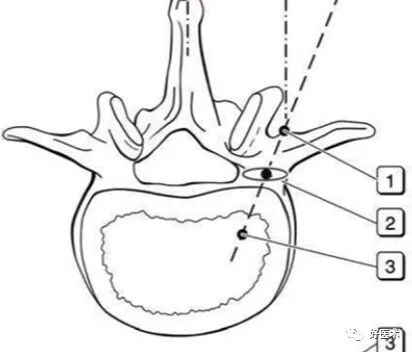

② 腰椎正位片子,猫眼是椎弓根椎狭窄部位的投影,按照操作手册,椎弓根螺钉偏内,容易损伤关节突关节面;

透视判断椎管

透视腰椎正位:上下终板成单边;椎弓根(猫眼)对称;棘突居中。

透视腰椎侧位:上下终板成单边;椎弓根上下缘单边;椎体后缘成单边。

实际情况:没有专业的手术透视工作人员;正位和地面垂直;侧位和患者垂直;正位看猫眼内外,侧位看椎弓根上下。

判断:透视正位,椎管外的长度设定为A;透视侧位,椎体外的长度设定为B;如果A大于或者等于B,定位针不在椎管内;如果A明显小于B,定位针在椎管内。